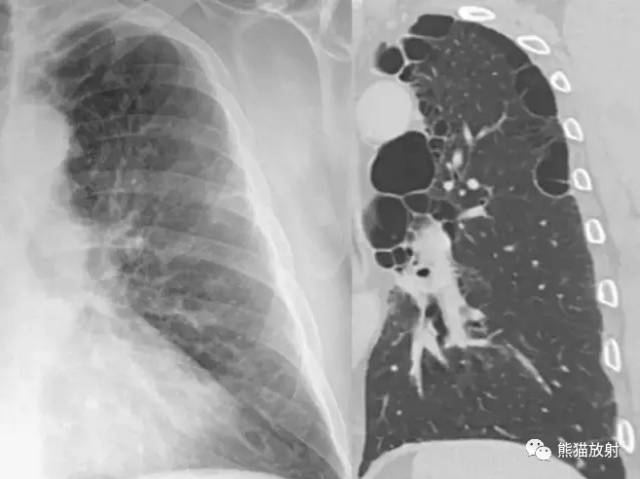

肺大泡是因小支气管活瓣性阻塞,肺泡过度膨胀、破裂互相合并而成,其直径大于1cm。肺小泡是指脏层胸膜内的积气,其直径最大1cm。

肺大泡X线表现为:薄壁环形透光区,壁薄如线,常只能见到部分囊壁,甚至有时不易见其囊壁,只见局限性透亮区,其中无结构。巨大的肺大泡可压迫周围肺组织,使囊壁增厚。

肺大泡可单发或多发,大小不一,多位于肺的周边,以肺尖、肺底常见。较小的大泡CT可明确显示。成年人进行性巨大肺大泡,称为肺消失征。肺大泡即可见于弥漫型肺气肿,亦可见于局限性阻塞性肺气肿。

| 间隔旁型肺气肿 |